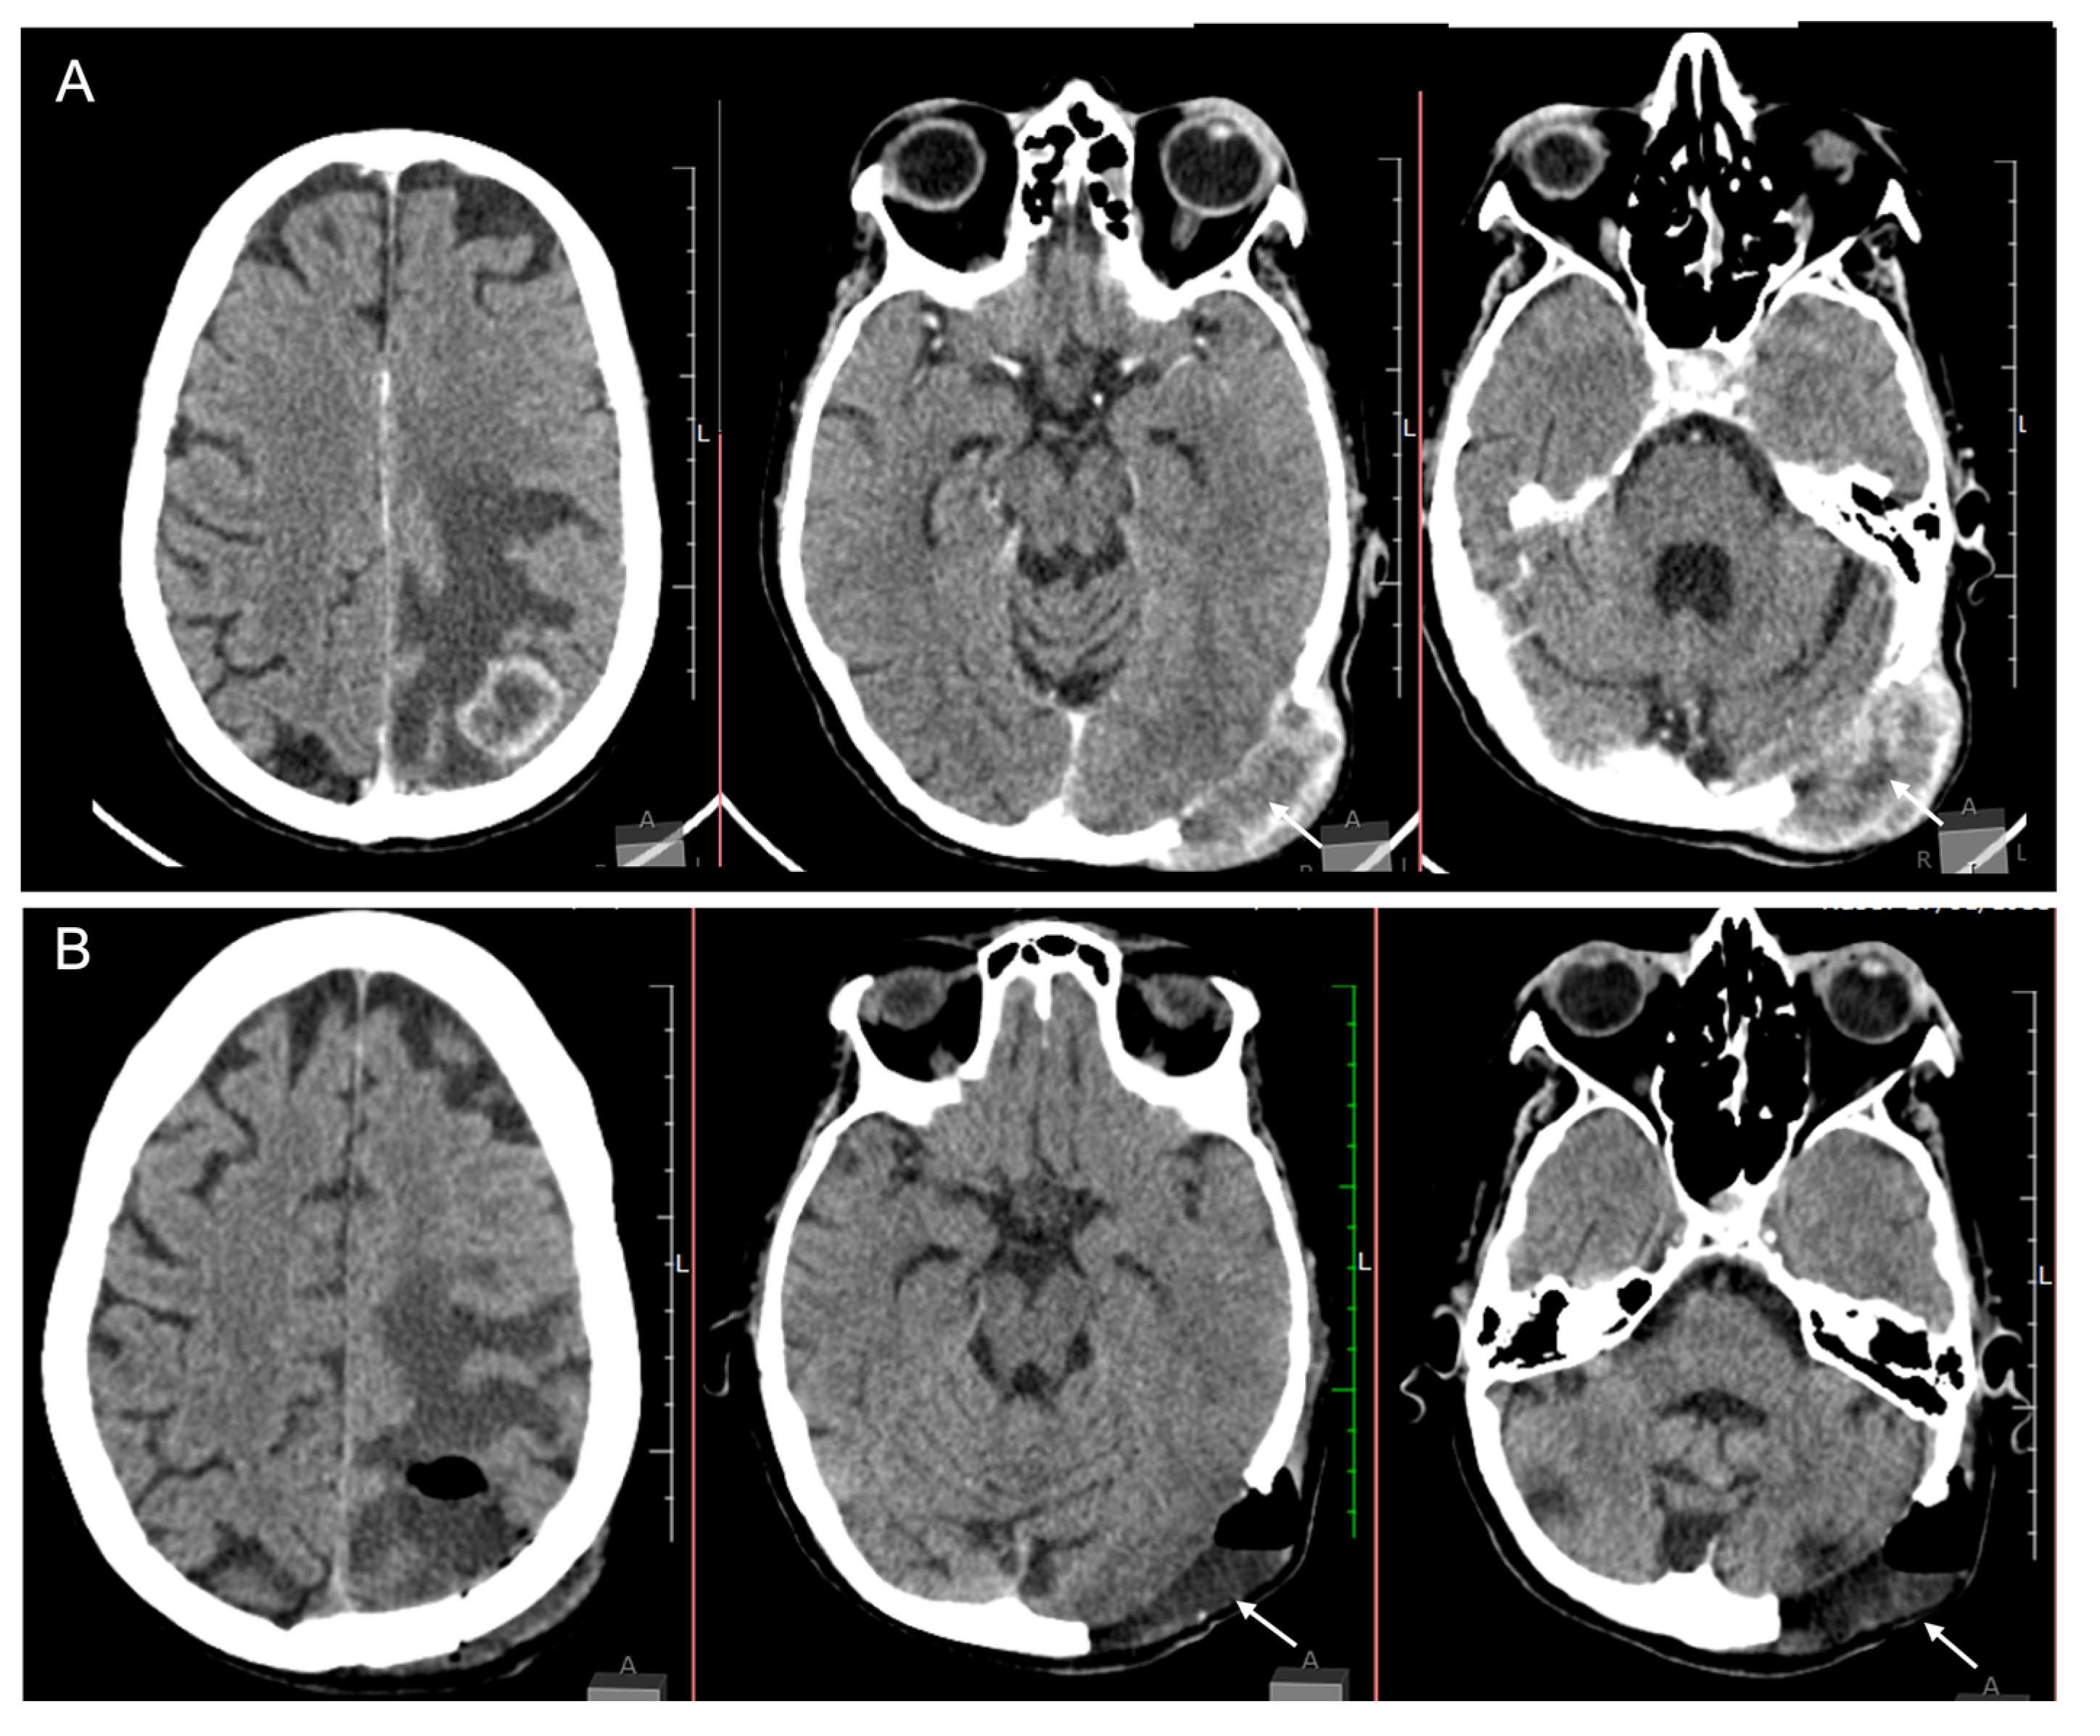

A brain CT scan revealed a parietal-temporal-occipital (PTO) lesion and a transcranial tumour (Figure 2). She underwent the surgical procedure to remove both lesions resulting in deficit improvement.

Figure 2.

Computer tomography (CT scan) of the brain showing pre- (A) and postoperative images (B). (A) CT scan with venous contrast showing an intra-axial lesion on the occipital/parietal lobes and an infiltrative transcranial lesion in the occipital bone. (B) Postoperative image of both intracranial and transcranial lesions.